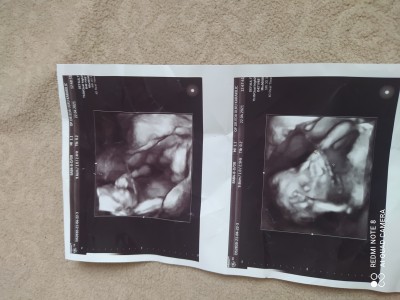

Resme bakar mısınız

Cinsiyeti ne acaba

Gebelik haftası

18

%50kiz %50 erkek

Bana kız gibi geldi

Doktor yüzde 99 kız dedi yanılma ihtimali olmaz inşallah ya gönlümden kız geçiyor ilk çocuğum erkek

Bence de kız

pipi diğilmi o

Canım bacak arası pek gözükmüyor sanki.ama kıza benziyor hayırlı evlat olsun

Amin inşallah ya doktorda kız dedi yüzde 99

Bacak arasını pek açmamış ama banada kız gibi geldi

Doktor yüzde 99 kız dedi ya kesin deseydi:)

Erkek. Bence. Cok net beli

Doktor yüzde 99 kız dedi